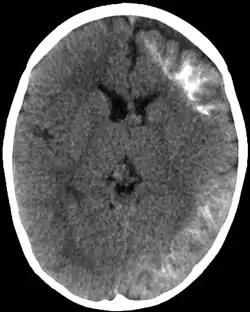

CT scan of Sturge-Weber syndrome

Sturge–Weber is an embryonal developmental anomaly resulting from errors in mesodermal and ectodermal development. Unlike other neurocutaneous disorders (phakomatoses), Sturge–Weber occurs sporadically (i.e., does not have a hereditary cause). It is caused by a mosaic, somatic activating mutation occurring in the GNAQ gene.[2] Imaging findings may include tram track calcifications on CT, pial angiomatosis, and hemicerebral atrophy.[3]

CT and MRI are most often used to identify intracranial abnormalities. When a child is born with a facial cutaneous vascular malformation covering a portion of the upper or the lower eyelids, imaging should be performed to screen for intracranial leptomeningeal angiomatosis. The haemangioma present on the surface of the brain is in the vast majority of cases on the same side as the birth mark and gradually results in calcification of the underlying brain and atrophy of the affected region.[5]